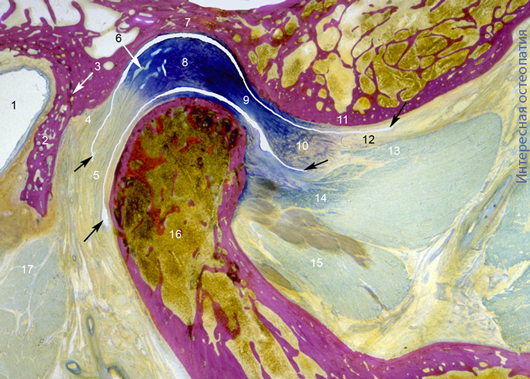

Рис. Сагиттальный срез правого височно-нижнечелюстного сустава. Рот закрыт.

1 — наружный слуховой проход, 2 — барабанная часть височной кости, 3 — барабанно-чешуйчатая щель fissura tympanosqumosa, 4 — волокна верхней части биламинарной зоны, 5 — нижние волокна биламинарной зоны, 6 — позади дисковое венозное сплетение, 7 — нижнечелюстная ямка, 8 — задняя часть диска, 9 — промежуточная зона диска, 10 — передняя часть (пояс, зона) диска, 11 — суставной бугорок височной кости, 12 — волокна сухожильные волокна перед диском, 13 — мышечные волокна к диску верхней головки латеральной крыловидной мышцы, 14 — мышечные волокна к челюсти верхней головки латеральной крыловидной мышцы, 15 — нижняя головка латеральной крыловидной кости.